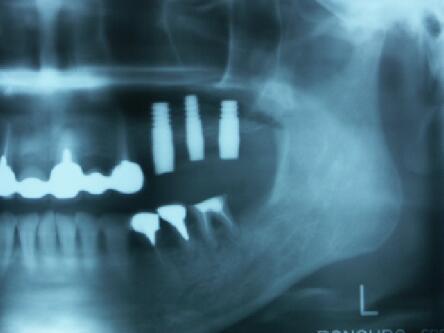

術前エックス線写真と口腔内写真

この方も上顎洞の下縁の骨が1~3ミリ程度しかなくソケットリフトでは不可能なのでサイナスリ フトの選択となる

インプラント埋入2ヵ月後のエックス線写真と口腔内写真

インプラント体(フィクスチャー)の周りに骨が出来始めている